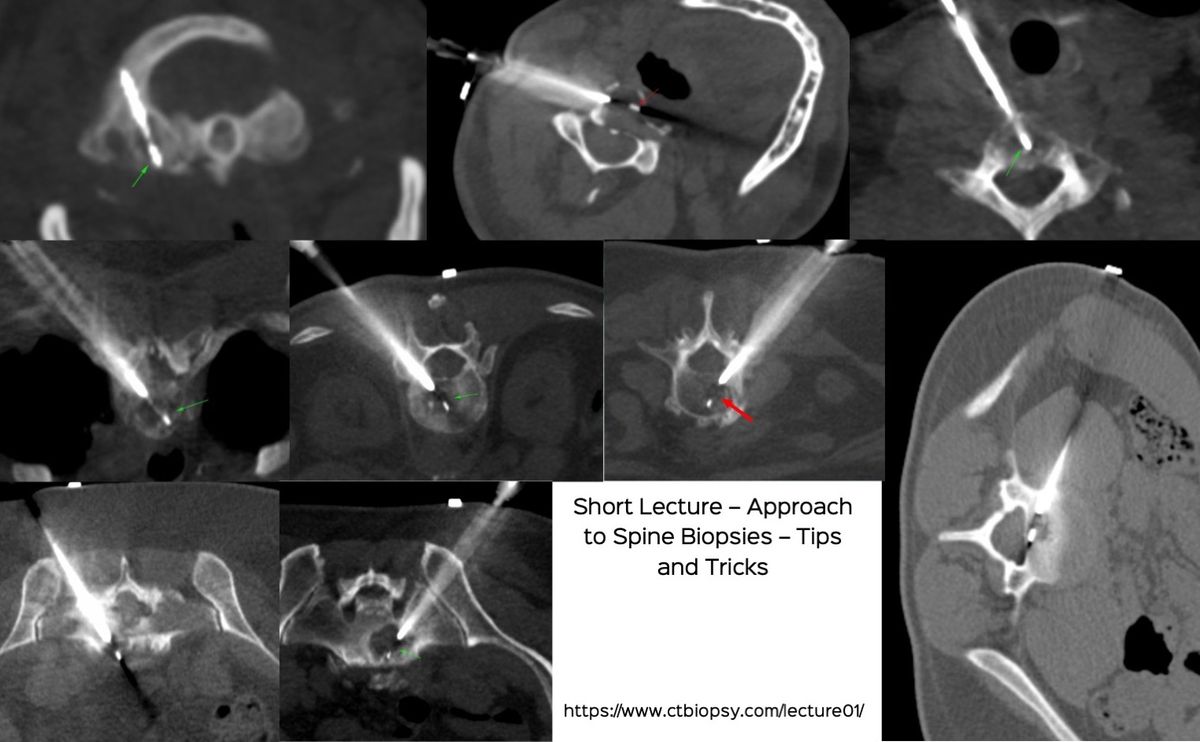

Lecture: Spine Biopsies - Tips and Tricks

Spine biopsies are simple, but need a little planning to arrive at the right approach to safely get as much material as possible for the diagnosis.